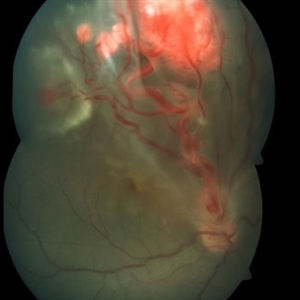

Retinal Capillary Hemangioblastoma

Fundus photograph of an 18-year-old Asian Indian male with multiple retinal capillary hemangiomas with sub retinal fluid.

Photographer: M S KRISHNA

Imaging device: Zeiss FF4

Condition/keywords: retinal angioma, retinal capillary hemangioma, tumor, Von Hippel-Lindau